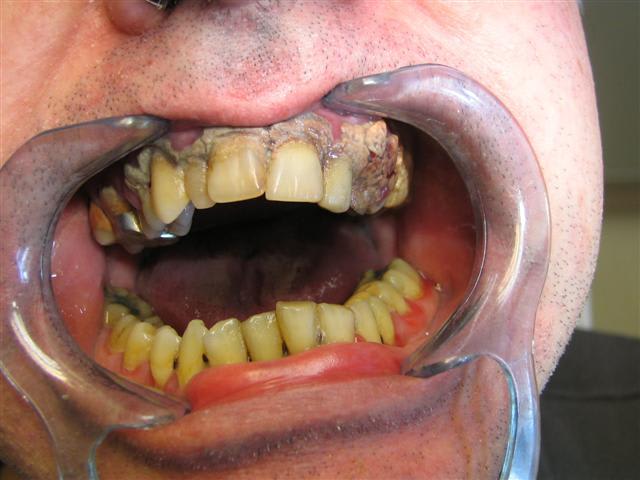

Ma petite contribution au show...

Et encore les photos ont été prises après une première séance de détartrage mandibulaire :-( (c'était le même topo qu'au maxillaire)

Devinez quelle fut l'"excuse" du patient pour avoir laissé tout ce tartre depuis si longtemps???

Juste une remarque: en bas le tartre est parti mais les depôts mous sont deja de retour et donc le mec se brosse pas les dents.... pourquoi tu perds du temps avec lui?

En fait son excuse était que au niveau de la 13 il a (avait) une CIV avec facette en résine et que sa facette ne "tenait pas" selon lui et qu'elle avait été "recollée" plusieurs fois par le passé donc il a laissé le tartre recouvrir ça pour camoufler....mouaiffff

Bon, le patient avait pas l'air très net au niveau psychologique ;-)

et en plus il est alcoolique...